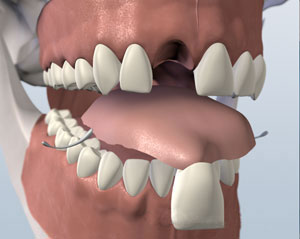

Multiple Tooth Dental Implants

A multiple-tooth dental implant is similar to a single-tooth implant but replaces more than one tooth. It is especially helpful for individuals who have lost several teeth because it provides a natural look and feel without wearing a bridge or partial plate. Bridges and plates rely on the surrounding teeth for support, so they aren’t the best solution if more than one tooth is missing.

The procedure for a multiple implant is similar to that for a single implant. Instead of an individual replacement tooth, a custom set of attached teeth, similar to a bridge, is made and attached to abutments. These will screw into the implants so they are permanent and stable.